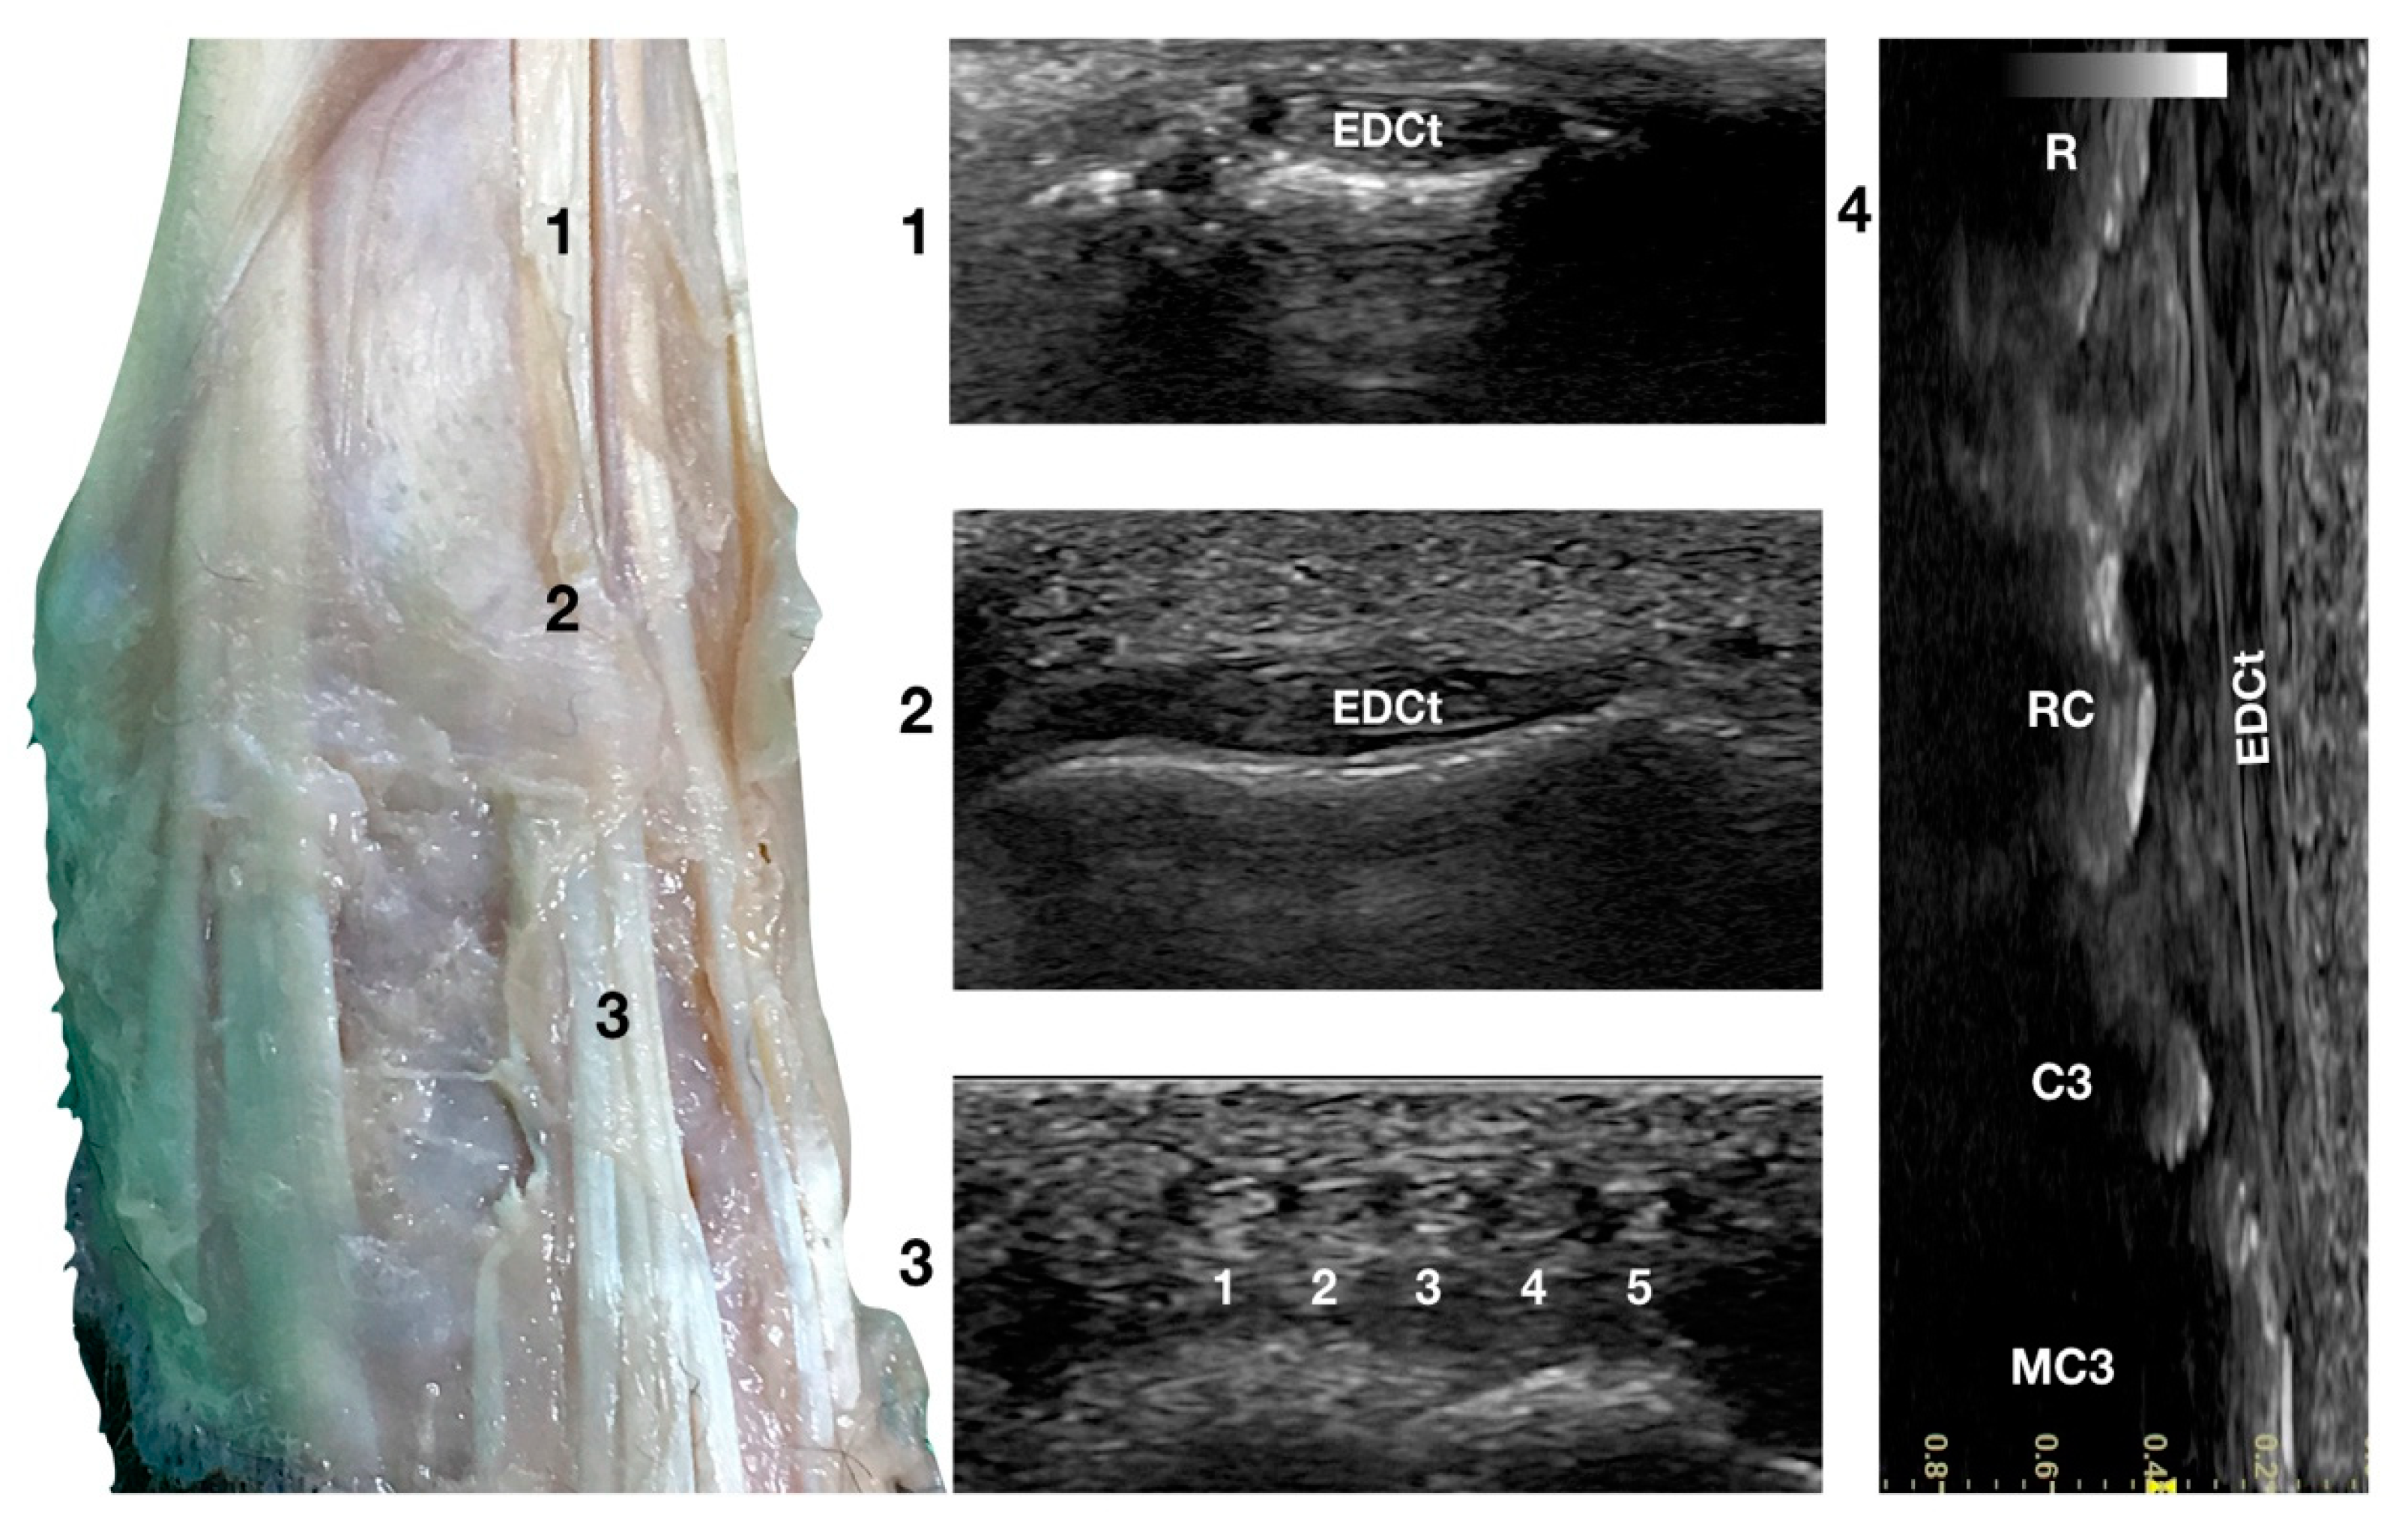

Just lateral to the groove of the Extensor Carpi Radialis tendon and lateral to the large accessory cephalic vein, in the more prominent but shallower Extensor Digitorum Communis groove, on the dorsal surface of the carpus, the Extensor Digitorum Communis tendon (EDCt) was palpated and easily visualised in a transverse scan plane (Figure 1a). At the ulnar notch level, the tendon is thin and flattened with a markedly oval shape and is easily recognised by the medially located, rounder, Extensor Carpi Radialis tendon (Figure 3).

Figure 3.

Dorsal carpal face centred on the Extensor Digitorum Communis tendon. At the ulnar notch level (2), the EDC tendon is thin and large, easily differentiated from the ECRt by its shape and position. Dorsally, just distal to the tenomuscular junction (1), the tendon is thicker and narrower. At the level of the radiocarpal joint (3), the tendon subdivides into four small tendons (white 2 to 5). The small, medial tendon of the Extensor Digiti I Longus is often visible (white 1). On the longitudinal scan plane (4), the fine fibrillar pattern of the thin tendon is visible. The image shows the part of the tendon that crosses the radius (R), the radiocarpal bone (RC), the carpal bone three (C3), and the third metacarpal bone (MC3).

In a transverse scan plane, sliding the probe proximally, the EDCt became rounder and thicker at the tenomuscular junction. Sliding the probe distally, the EDCt was enclosed in a common synovial tendon sheath and passed through the lateral distal sulcus of the radius. The Extensor Retinaculum was seen as a thick hyperechoic line. Most of the time, this structure was ultrasonographically indistinct from the tendon sheath. The Extensor Retinaculum surrounded the tendon and blended with the periosteum on the lip of the carpal articular surface. At the level of the radiocarpal joint, the uniformly flattened EDCt divided into four separate thin tendons. They passed on the dorsal surface of the corresponding digits, ending in the dorsal portion of the ungual crest of the distal phalanges. With the 18 MHz probe, it was possible to differentiate the small tendons clamped together from the intercarpal joints and which became more distinct structures when progressing distally.

The tendon of the Extensor Digiti I Longus was inconsistently seen medially. In this case, five small tendons were seen running distally on the dorsal surfaces of the metacarpal bones. The tendon thickness reduced sharply at the subdivision, and the distal portion of the tendons was often too thin to be visible on the transverse plane. At the same time, it was possible to see its termination on the longitudinal scan planes when the patient’s paw was elevated from the ground and the digits were extended. The tendons were thin, having a straight path and the typical fibrillar pattern. The extension and flexion of the digits helped to define the tendon insertion and assess tendon function, lesions, adhesion, and subluxation.

Just lateral to the EDCt at the ulnar notch of the radius, on a transverse scan, the Extensor Digitorum Lateralis tendon (EDLt) was seen as a small, oval to slightly rounded shaped structure (Figure 1a). It was more dorsomedially located than the more prominent Extensor Carpi Ulnaris tendon (ECUt), easily palpated on the lateral face of the carpus. It was the only tendinous structure lateral to the EDCt and medial to the ECUt. Proximally, the tendon maintained the same size and shape until the tenomuscular junction. Distally, at the intercarpal joint level, the homogeneous echogenicity of the tendon was interrupted by an oblique hyperechoic line that demarcated the two components arising from the united tendon (Figure 4).

Figure 4.

Dorsal carpal face centred on the Extensor Digitorum Lateralis tendon. At the ulnar notch level (2), the EDLt is seen as a thin oval tendon embedded in the deep Extensor Lateralis groove. Proximally (1), the tendon is thicker. The EDLt divides into two parts distally at the intercarpal joint (3). On the longitudinal scan plane (4), the fine fibrillar pattern of the thin medial tendon is visible. The bony surface beneath is recognisable. R, radius; RC, radiocarpal bone; C4, carpal bone four; MC4, fourth metacarpal bone.

The two parts of the EDLt passed through the groove between the distal ends of the radius and the ulna, over the dorsolateral border of the carpus to the metacarpus, and then diverged from each other. The two thin tendons (the medial is the smaller) passed over the dorsolateral surface of the corresponding metacarpal bones (third and fourth for the medial tendon, and the ulnar carpal bone for the lateral tendon). They ended on the dorsal surface to the distal phalanges of digits III, IV (the medial tendon divided into two branches), and V (the lateral branch). They were surrounded by a thick hyperechoic line (fibrous tendon sheath). The tendons, even if thin, were seen in the longitudinal scan until the mid-metacarpal diaphysis. It is possible that, in larger breed dogs, the tendon can be evaluated more distally. Elevating the foot from the ground and rotating the probe to check the longitudinal scan plane often helped in examining the distal portion. The extension and flexion of the lateral digits helped to better differentiate the tendon from the surrounding tissues and assess tendon function, lesions, adhesion, and subluxation.